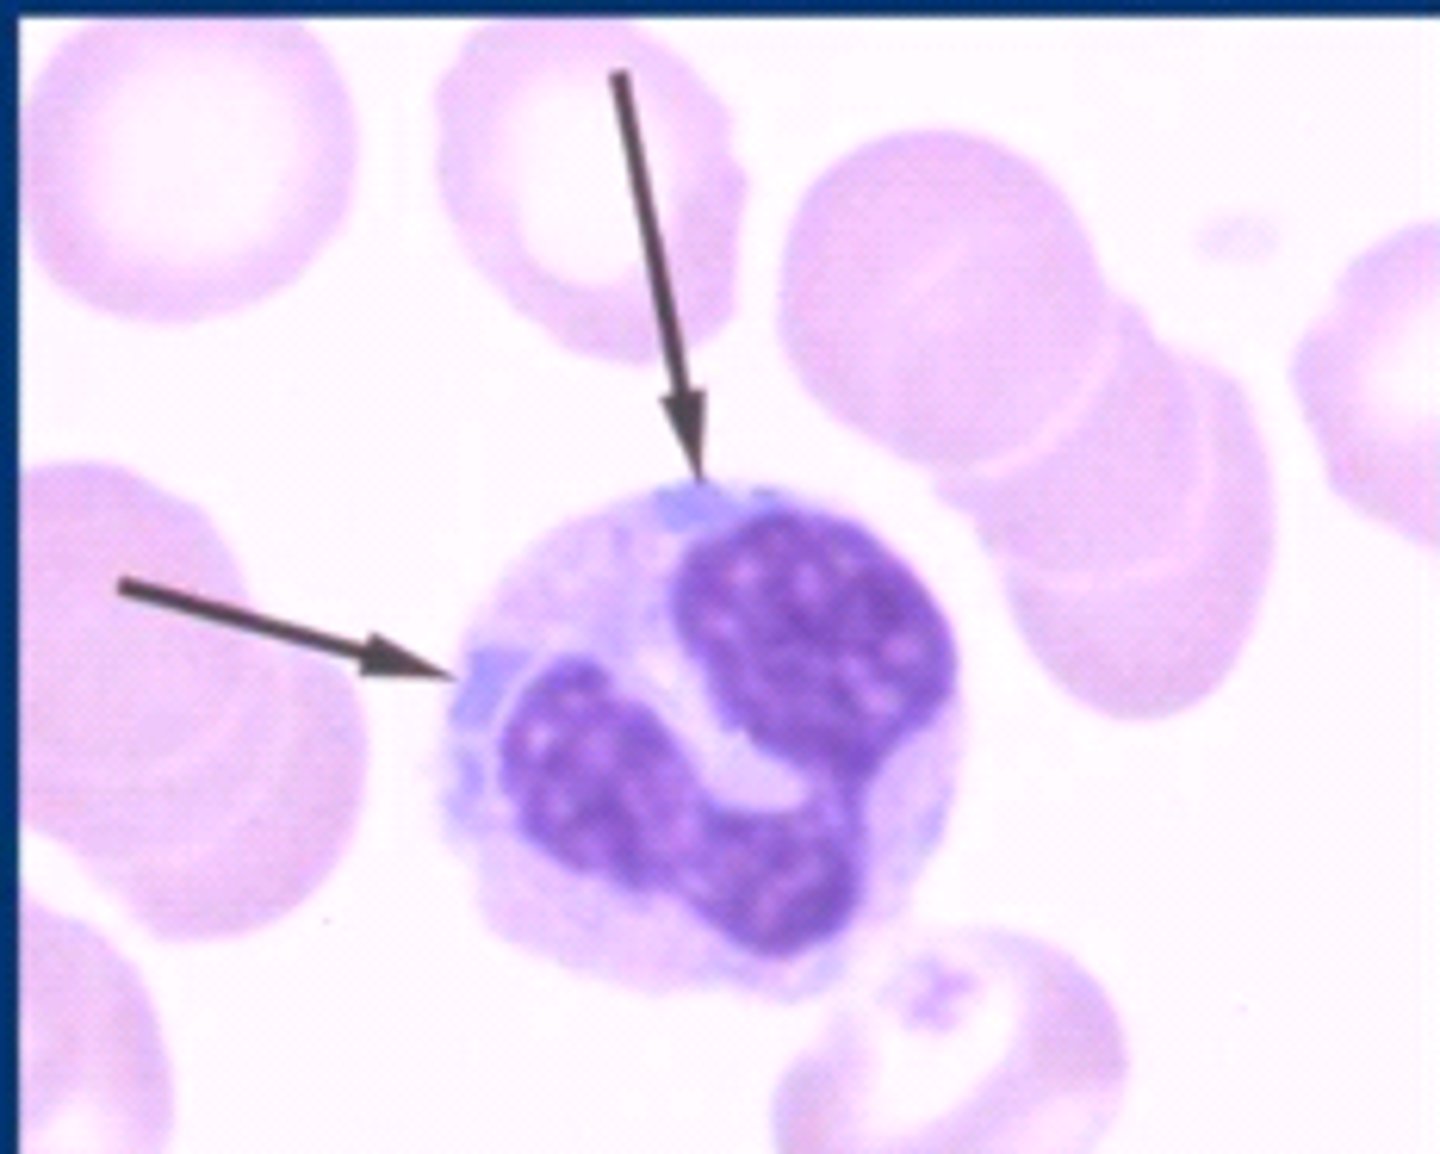

toxic neutrophils

MAMMAL

1. increase basophilia in cytoplasm

2. dohle bodies

3. vacuolated/foamy cytoplasm

4. +/- increase in cell size

dohle bodies

MAMMAL